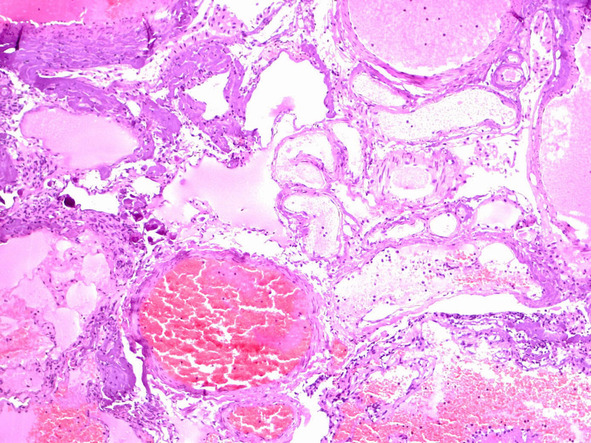

При рутинном исследовании в световом микроскопе (срезы толщиной 5 мкм, окраска гематоксилином и эозином, при необходимости – докрашивание по Ван-Гизон и Маллори) каверномы представляют собой конгломерат тонкостенных полостей разнообразной неправильной формы, выстланных эндотелием и разделенных соединительнотканными перегородками. Соединительная ткань перегородок может быть представлена как тонкими коллагеновыми волокнами, так и грубоволокнистой фиброзной тканью с различной степенью дистрофических изменений. Характерным признаком является отсутствие в стенах каверн гладкомышечных клеток и эластических волокон, а также мозговой ткани между кавернами (рис. 11) (2, 236, 299, 333).

Лишь в отдельных препаратах можно обнаружить незначительные прослойки мозговой ткани. Реактивно измененная мозговая ткань может быть также выявлена вокруг каверн, полностью отделенных, «отшнурованных», от основного конгломерата (рис. 12).

На основании этих признаков проводят дифференциальный диагноз каверном с другими сосудистыми мальформациями, прежде всего, с АВМ, при гистологическом исследовании которых выявляют сосуды артериального и венозного типа с относительно дифференцированными стенками и значительное количество мозговой ткани между ними.

Полости, образующие каверному, могут быть заполнены жидкой кровью либо тромбами в различной стадии формирования (рис. 13).

Рис. 11. Кавернозная мальформация «классического» типа — конгломерат сосудистых полостей различной формы и размеров, выполненных кровью. Ув. х 100